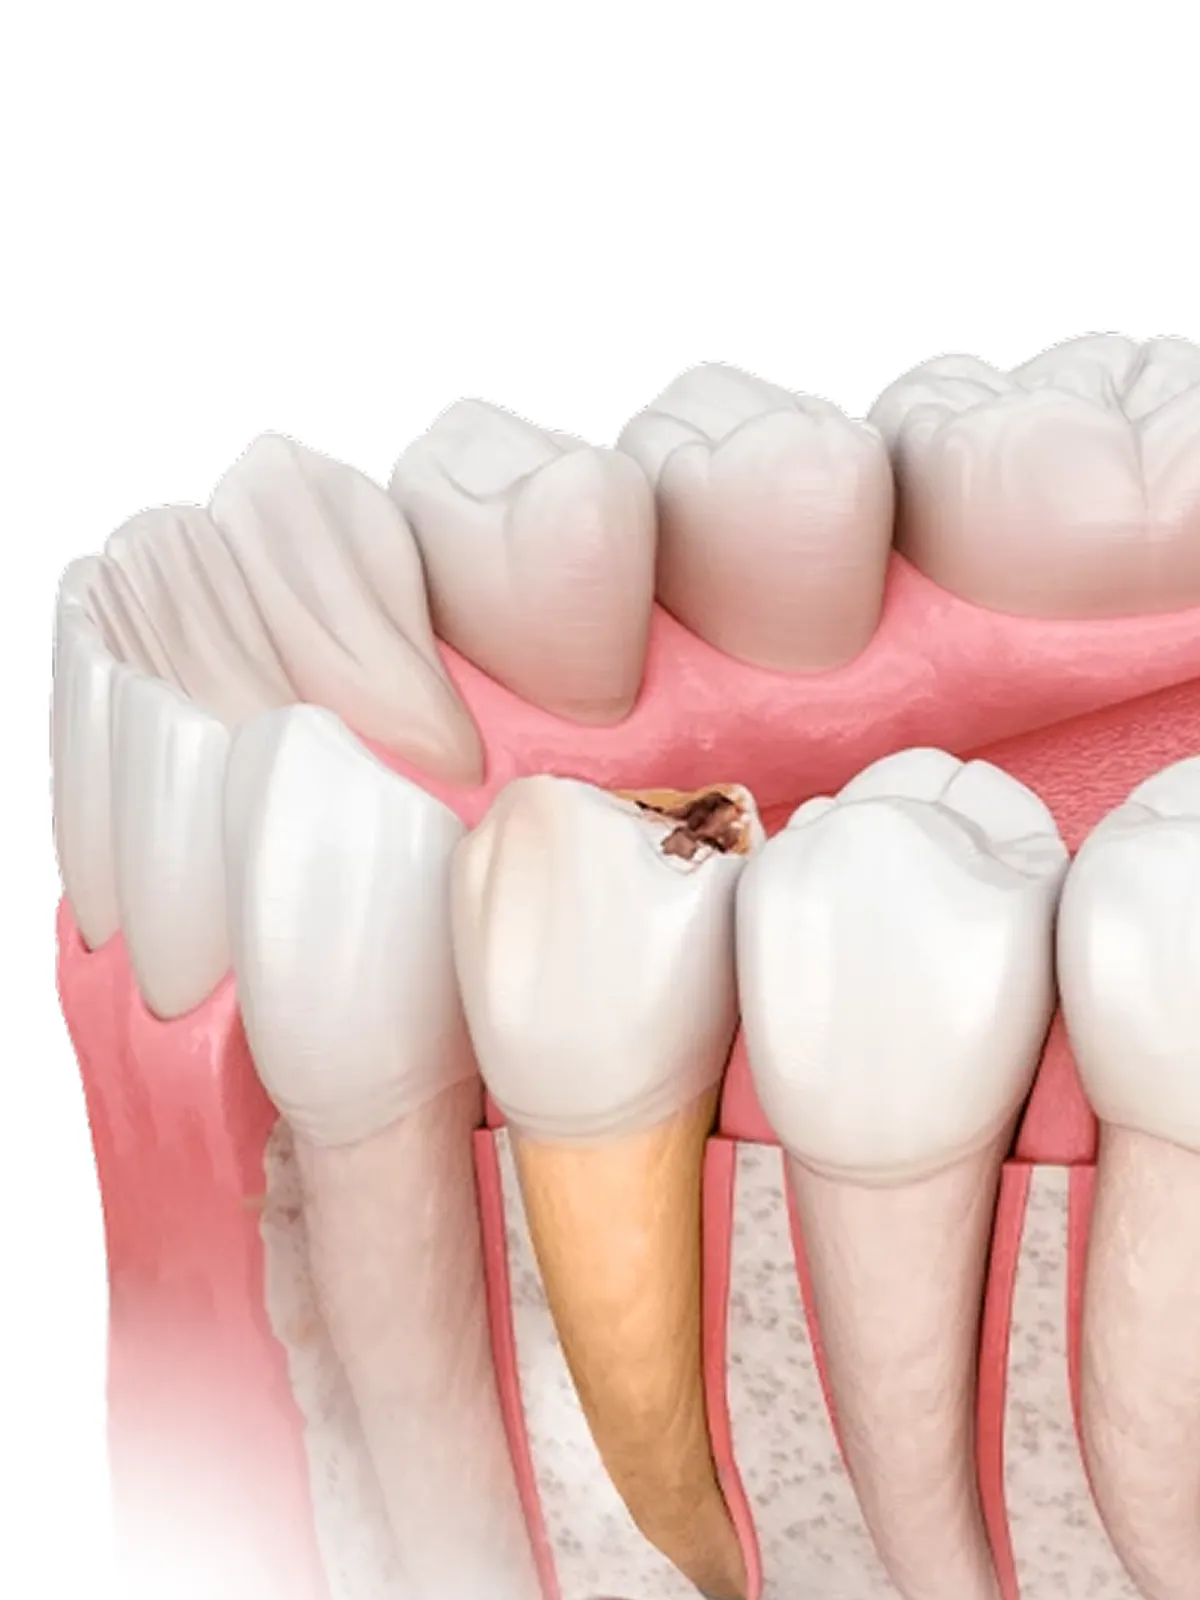

Видалення проводиться лише тоді, коли зберегти зуб неможливо або небезпечно.